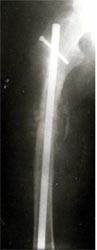

病例一、患者22岁,股骨中下1/3骨折骨不连2年,明显畸形。

X线片显示钢板螺钉已经松脱,固定失败,断端骨折端硬化

我们用髓内钉内固定后保证早期稳定性,植骨补充成骨所需基质,骨生长因子和骨髓细胞的植入,可分化成为骨痂组织,有效促进了骨不连的愈合